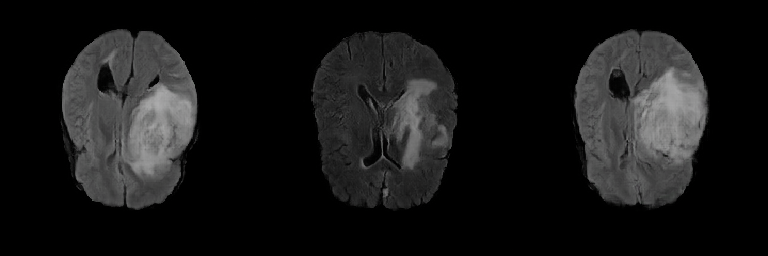

It can be seen from Figure 1 that the same organization is displayed differently in different modalities [22]. The brain tissue is relatively constant in the T1 and T2. The edema area is dark in the T1 modal, while the white shadow area is formed on the T2. The T1 pays more attention to the anatomical details of each tissue; The T2 can highlight the lesion area more clearly and retain a high signal to the cerebrospinal fluid [23]. FLAIR uses water suppression technology for imaging. Free water is a low signal (edema state), and bound water is a high signal (non-edema area) [22]. The FLAIR sequence can clearly show the lesions near the ventricle or near the cortex [24]. That is useful for observation in the diagnosis of diseases such as gliomas. Therefore, this work mainly focuses on the FLAIR sequence generation of gliomas images.

This research exploits the BRATS 2019 training dataset containing 259 High-Grade Gliomas (HGG) cases. We select the 64th slice among the whole 155 slices as the initial/final slices will convey a negligible amount of information and affect the training [32]. Therefore, the training dataset is 259 FLAIR brain axial (AXI) MR images, zero-padded to 256 x 256 from original-sized 240 x 240 pixels for better GAN training. Figure 4 shows real FLAIR samples.